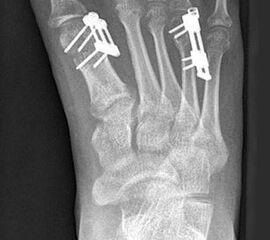

Das im Folgenden vorgestellte Operationsverfahren beschreibt die Kallusdistraktion von Metatarsalia nach den Prinzipien von Ilisarov 21 unter Verwendung eines internen, winkelstabilen Titan-Minifixateur (Klauser 2009). Der interne Distraktor ermöglicht während der Distraktions- und der Durchbauungsphase aufgrund seiner hohen Stabilität je nach Modell (18 mm, 23 mm) eine Verlängerung von bis zu 25 mm. Nach interner Anlage des Minifixateurs, meist lateral, kann über eine kontinuierliche Kallusdistraktion der Metatarsalebogen unter frühzeitiger Mobilisation im Gips oder Short-Walker rekonstruiert werden 15. Über einen interdigital und transcutan ausgeleiteten Aktivatorstab wird die Distraktion vom Patienten selber täglich morgens und abends durchgeführt. Zusätzlich vorliegende Strahlpathologien, wie zum Beispiel eine verkürzte Strecksehne oder ein kontraktes Metatarsophalangealgelenk können im Rahmen der Erstoperation ebenso therapiert werden wie z.B. ein Hallux valgus, ein Hallux valgus interphalangeus und/oder ein Digitus quintus varus (Klauser 2009). Nach Rekonstruktion des Metatarsalebogens wird in einem zweiten, kleinen Eingriff der Aktivatorstab über eine Spezialpinzette diskonnektiert und entfernt, wobei der Distraktor als interne Fixation belassen wird. Die Entfernung des Distraktors erfolgt in der Regel nach 9 – 12 Monaten, da es sich meist um angeborene kindliche Fehlbildungen handelt (Brachymetatarsie) und eine operative Intervention frühzeitig im Kindesalter erfolgen sollte (Klauser 2009).

• Simultane Behandlung eines doppelstrahligen longitudinalen Reduktionsdefektes möglich 113 (Klauser 2009).

Meist kam ein 18mm Minifixateur zur Anwendung und ausnahmslos wurde er lateral am Metatarsale implantiert. Bis auf das Metatarsale 5 wurden vom Autor alle weiteren Metatarsalia (MT1 – MT4) isoliert oder kombiniert verlängert. In 7 Fällen wurde eine simultane Verlängerung zweier Metatarsalia (2x MT1 und MT4, 4x MT3 und MT4, 1x MT2 und MT3) vorgenommen. Bei einem Großteil der Patienten musste eine Strecksehnenverlängerung entweder im Rahmen der Erstoperation oder im Rahmen der Aktivatorentkopplung vorgenommen werden. In neun Fällen (ausnahmslos bei Erwachsenen > 30 Jahre) sogar 2x sowohl während des Erst- als auch Zweiteingriffes. Annähernd regelhaft sind bei den eben genannten Eingriffen Arthrolysen des Metatarsophalangealgelenks des betroffenen Zehenstrahls erforderlich, da durch die Distraktionsverlängerung eine hohe Kompression auf das jeweilige Grundgelenk entsteht.